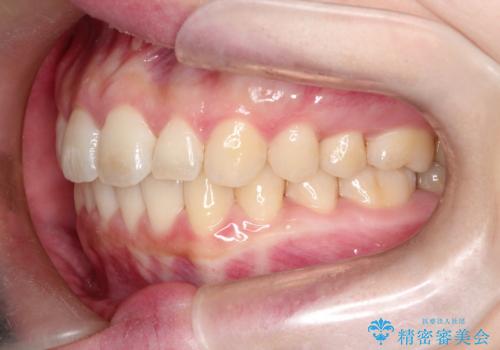

【インビザライン】前歯が出てるのを治したい

- 前歯の凸凹と前突を主訴に来院されました。

インビザラインにて治療をおこない、歯並びを改善することができました。